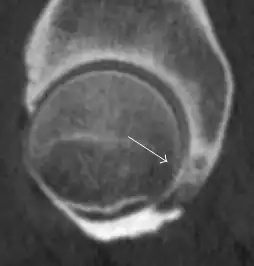

Most of the angles and measurements described in the plain radiograph section can be accurately reproduced on MRI. In addition, the superiority of MRI resolution with intra-articular contrast allows detection of labral and chondral abnormalities that may influence the choice of medical, percutaneous, or surgical management (Figure 9).[1]

Sagittal T1 weighted image showing anterosuperior labral tear.[1] -

Sagittal T1 weighted image showing chondral lesion.[1] -